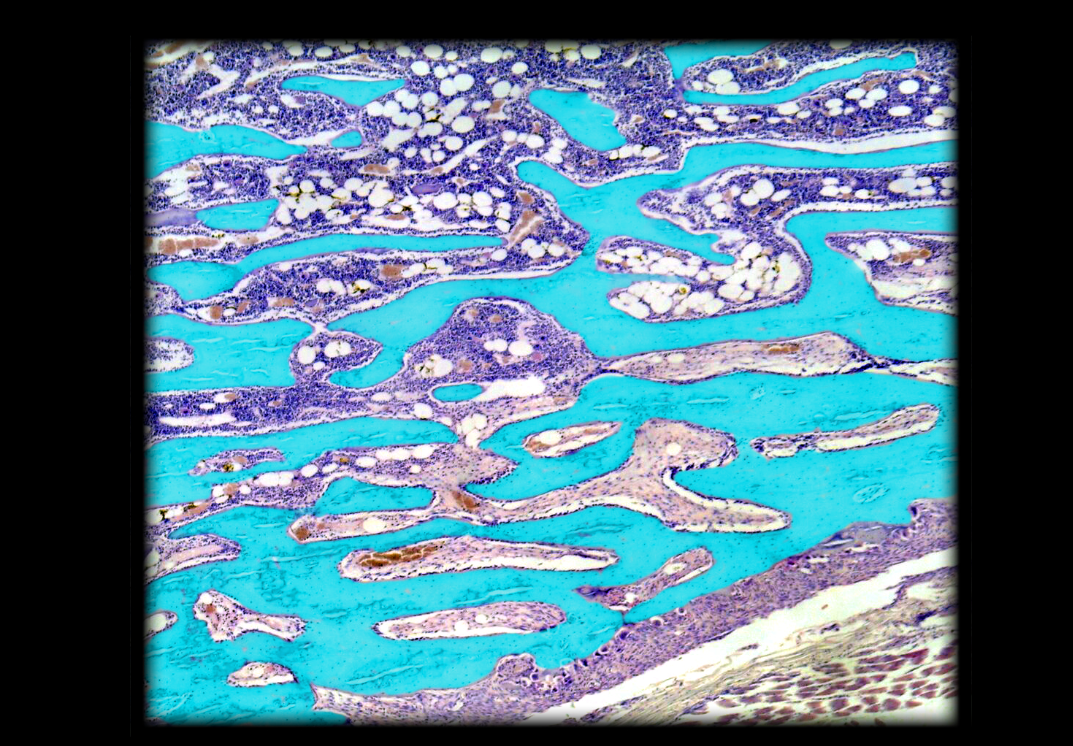

Lacuna (with chondrocyte) in hyaline cartilage

Marrow cavity in spongy bone

Trabecula of spongy bone

Chondrocyte (in lacuna) in hyaline cartilage